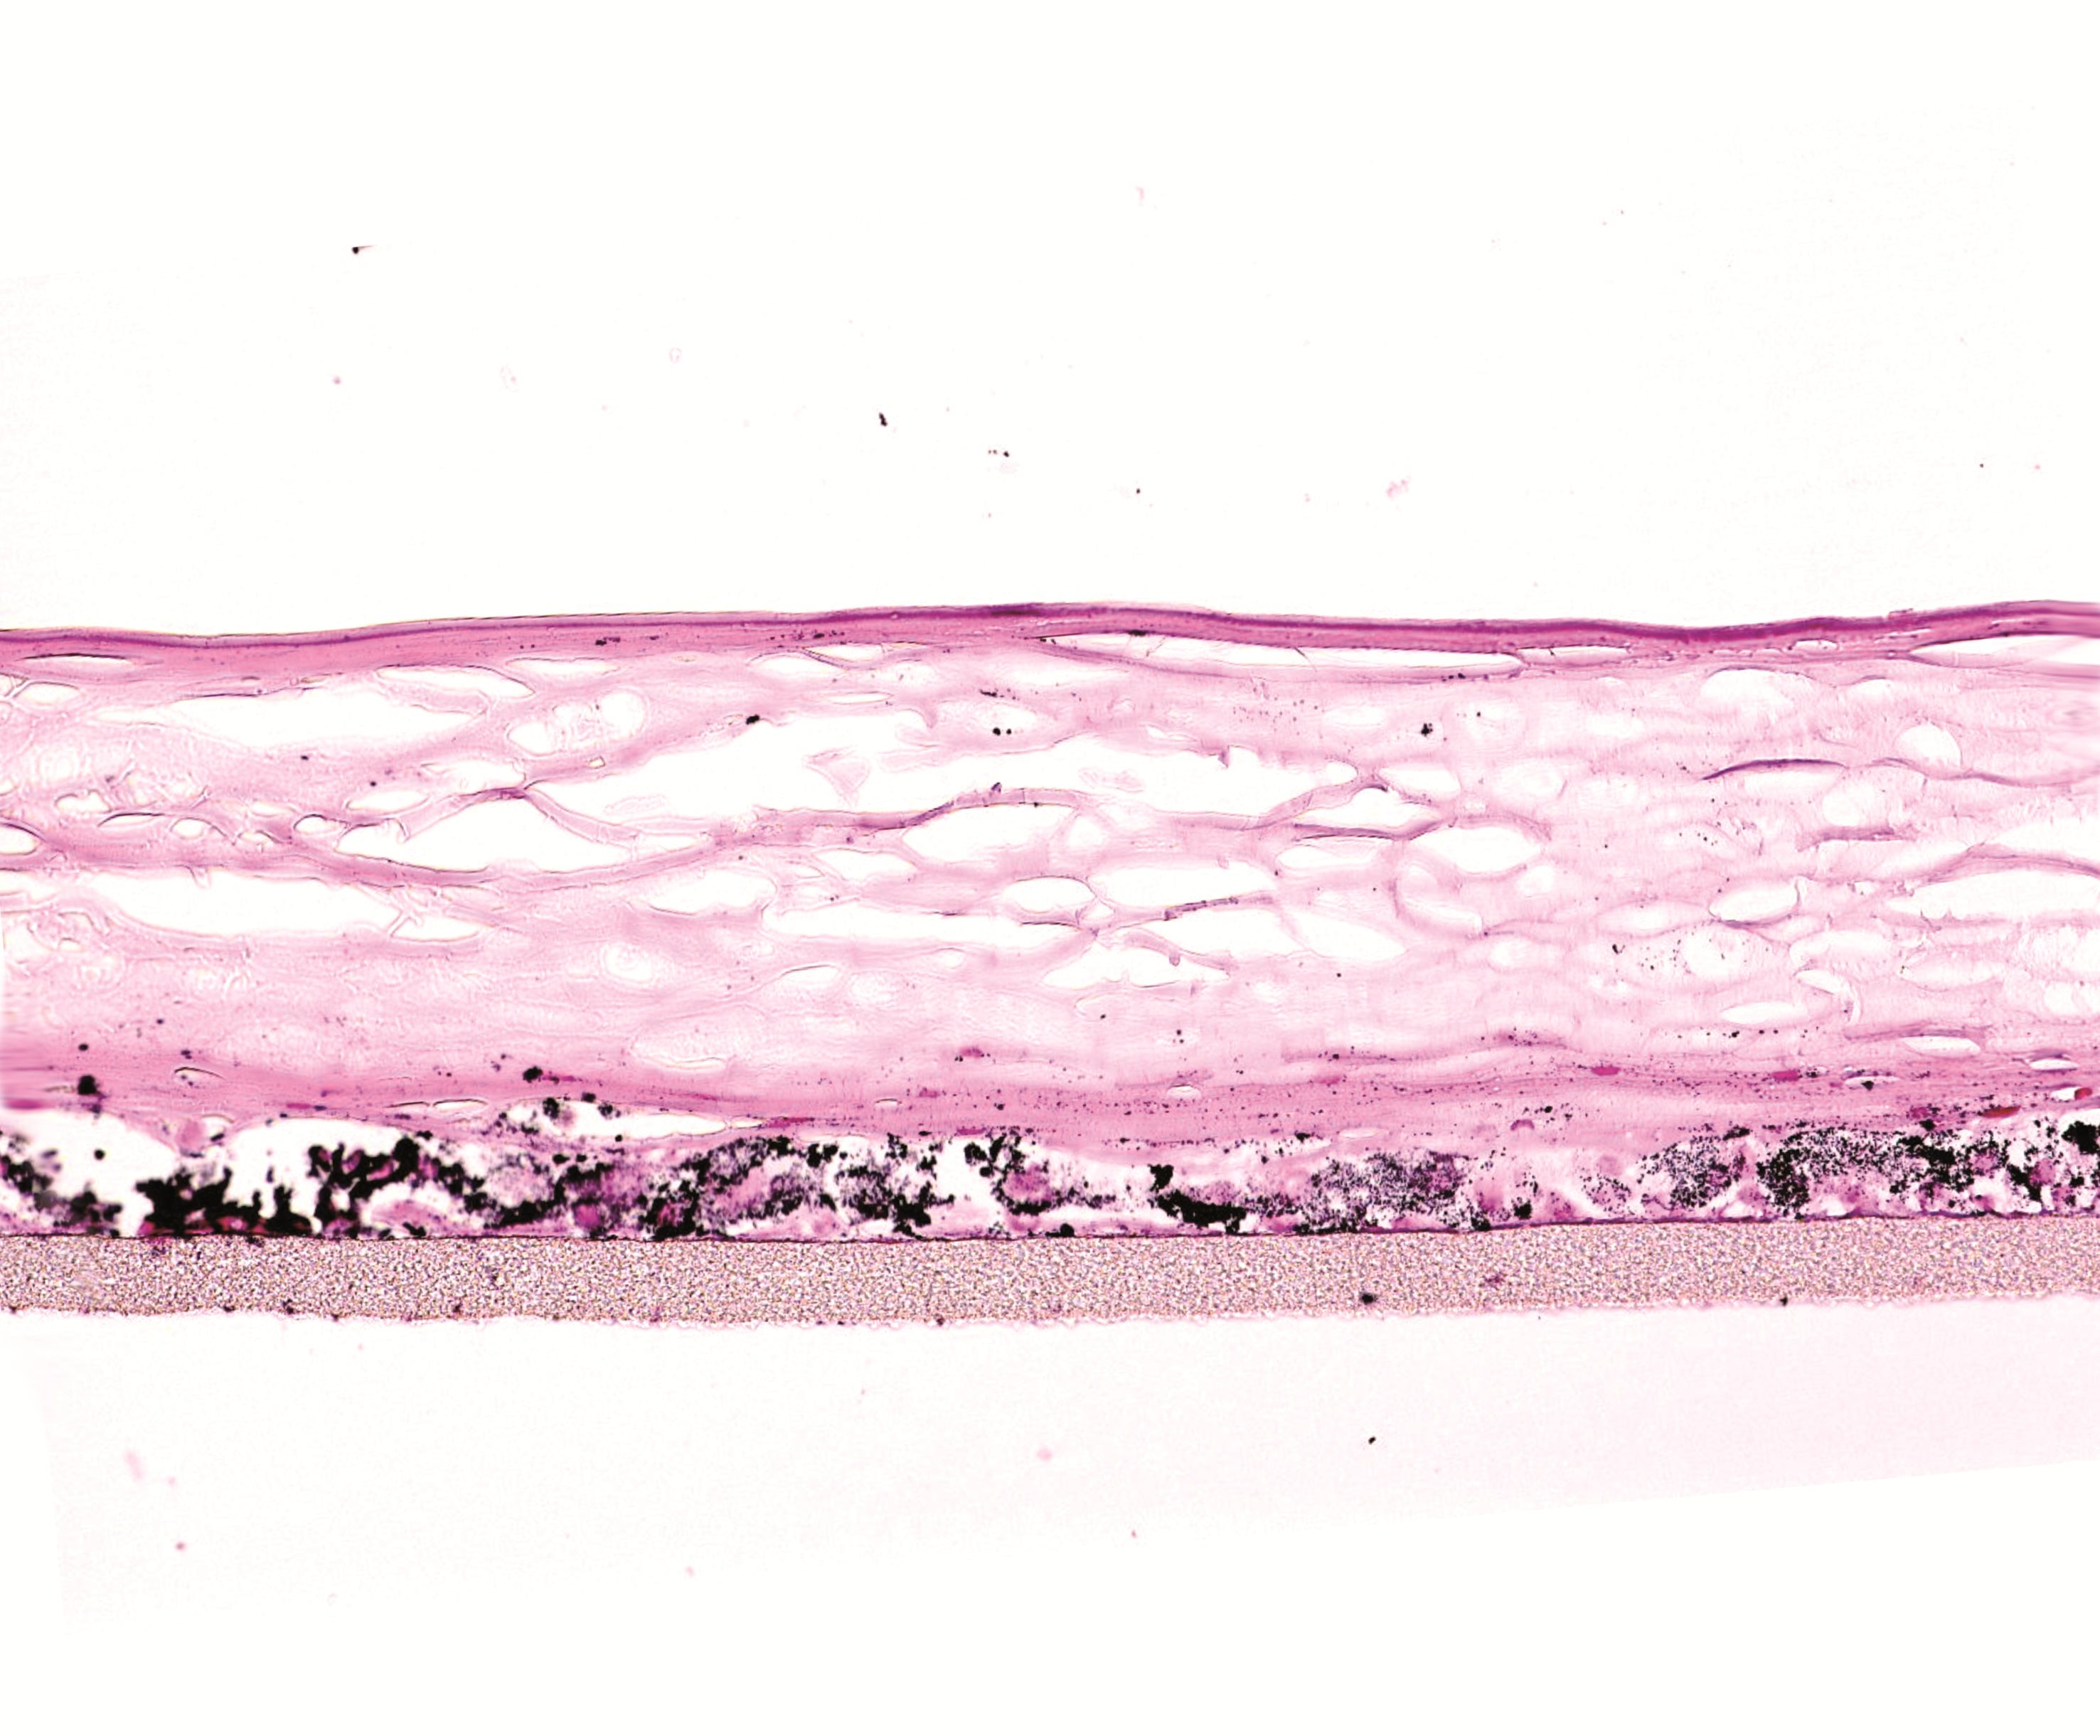

Petele pigmentare sunt o preocupare tot mai des întâlnită, indiferent de vârstă sau tip de ten. Expunerea îndelungată la soare, dezechilibrele hormonale sau procesul natural de îmbătrânire stimulează producția excesivă de melanină, ducând la apariția acestor imperfecțiuni. Deși nu sunt periculoase, ele pot afecta uniformitatea și luminozitatea pielii.